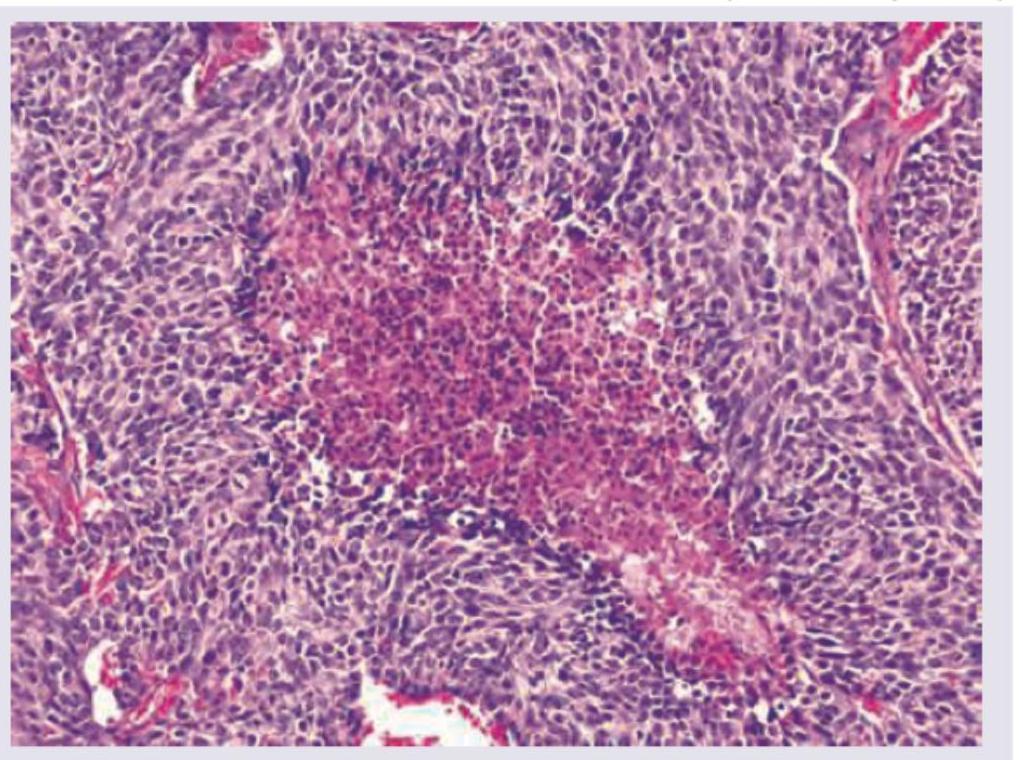

Question 2: A 55-year-old male patient presented with a 4 month history of cough and hemoptysis. Bronchoscopy revealed an intrabronchial polyp. Biopsy from the polyp showed small cells with salt and pepper chromatin, with microscopic necrosis and 5 mitotic figures per 10 high power fields as shown below. Chromogranin staining was positive. What is the diagnosis and grade of the lesion?

- D. Atypical carcinoid grade 2 (Correct Answer)

Explanation: ***Atypical carcinoid grade 2*** - The presence of **salt and pepper chromatin**, **microscopic necrosis**, and **5 mitotic figures per 10 high power fields** are characteristic features of an **atypical carcinoid tumor** [1]. - **Positive chromogranin staining** confirms neuroendocrine differentiation, and the mitotic rate coupled with necrosis indicates a Grade 2 (atypical) carcinoid based on WHO classification [1]. *Carcinoid grade 1* - A typical carcinoid (Grade 1) would show **no necrosis** and a mitotic count of **less than 2 mitoses per 10 high power fields**, which contradicts the findings [1]. - While it features **salt and pepper chromatin** and positive neuroendocrine markers, the higher mitotic activity and necrosis exclude a typical carcinoid. *Small cell carcinoma grade IV* - **Small cell carcinoma** typically presents with extensive necrosis, very high mitotic activity (often >10 mitoses/10 HPF), and a more **scanty cytoplasm** than seen here, and often **crush artifact** [2]. - Although it is a high-grade neuroendocrine tumor, the described features (only 5 mitoses/10HPF, "salt and pepper chromatin" is less typical for SCLC which has more uniform nuclei, and distinct necrosis without widespread crush artifact) are more consistent with an atypical carcinoid [1], [2]. *Large cell neuroendocrine carcinoma grade IV* - **Large cell neuroendocrine carcinoma** (LCNEC) is characterized by **large cells** with prominent nucleoli, high mitotic counts (often >10-11 mitoses/10HPF), and extensive necrosis [2]. - The "small cells" and **salt and pepper chromatin** described in the biopsy are inconsistent with the large cell morphology of LCNEC. **References:** [1] Kumar V, Abbas AK, et al.. Robbins and Cotran Pathologic Basis of Disease. 9th ed. The Lung, pp. 725-727. [2] Cross SS. Underwood's Pathology: A Clinical Approach. 6th ed. Common Clinical Problems From Respiratory Tract Disease, pp. 337-338.